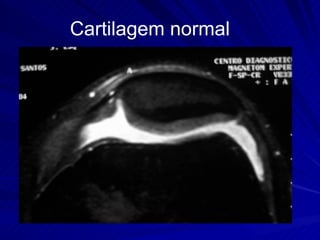

Cartilagem normal